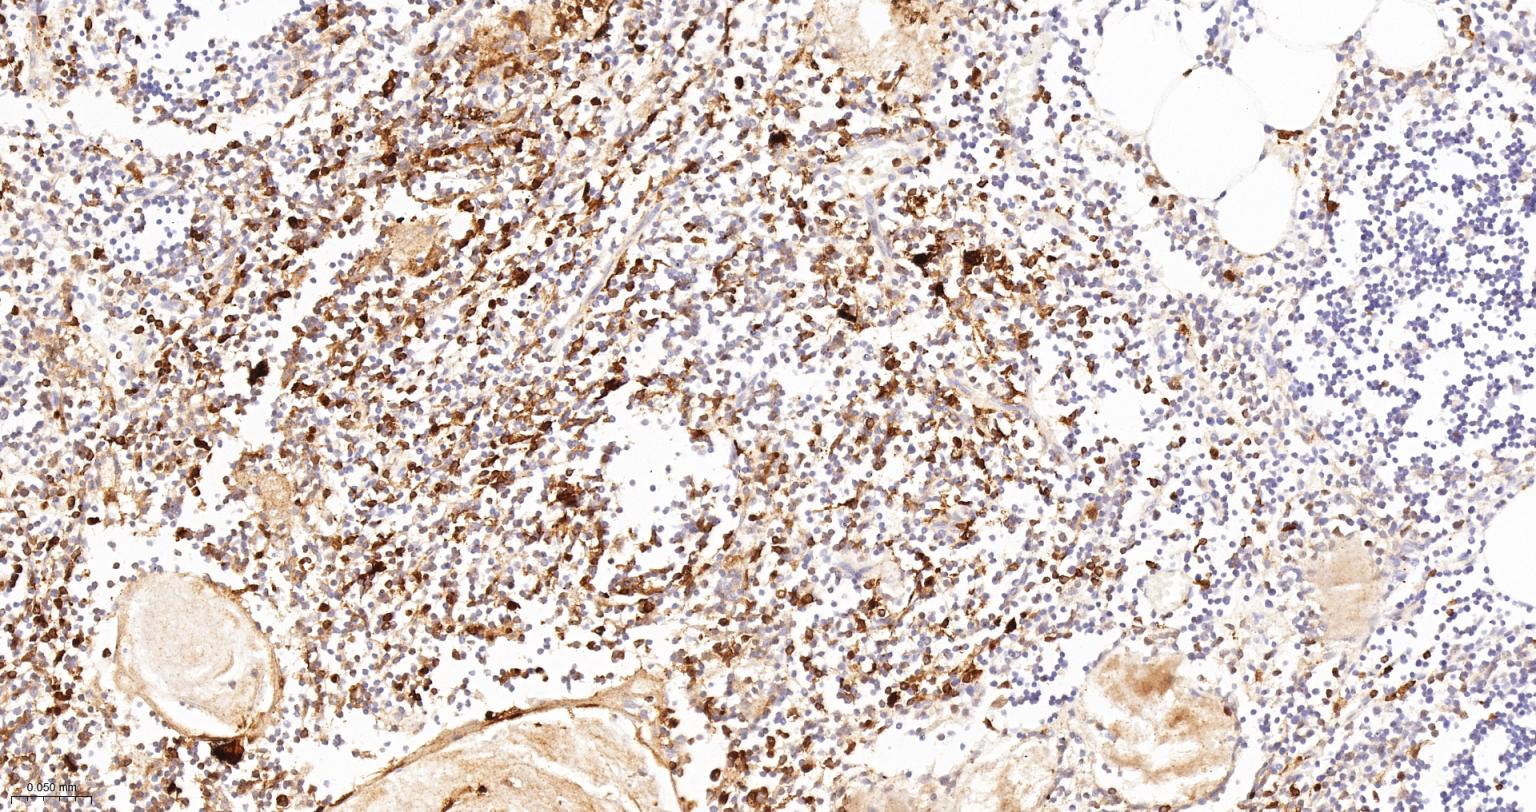

Paraformaldehyde-fixed, paraffin embedded Rat Spleen; Antigen retrieval by boiling in sodium citrate buffer (pH6.0) for 15 min; Antibody incubation with CD16 Monoclonal Antibody, Unconjugated(bsm-54679R) at 1:400 overnight at 4°C, followed by conjugation to the bs-0295G-HRP and DAB (C-0010) staining.